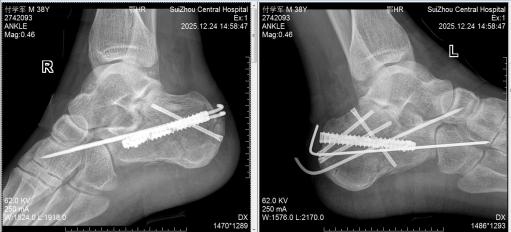

图4术后双跟骨X线